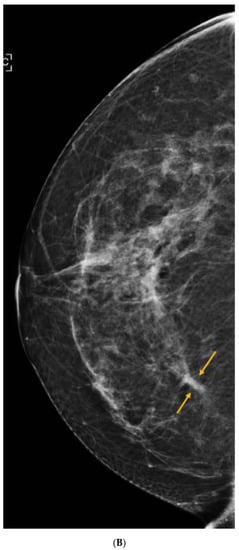

8. Contrast-Enhanced Mammography (CEM)